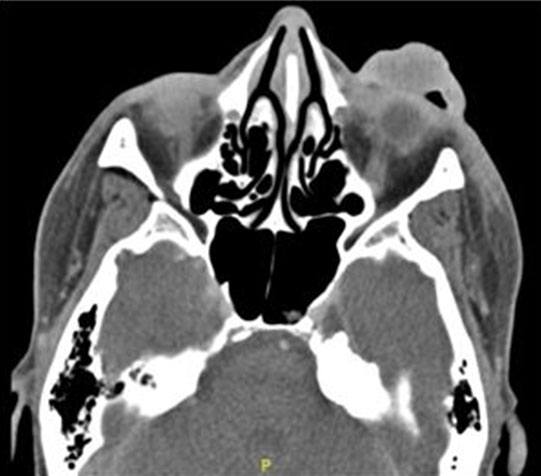

Serologic workup showed a normal white blood cell count with lymphopenia and neutrophilia, consistent with her lymphoma. In addition, inflammatory markers were elevated with an erythrocyte sedimentation rate (ESR) of 116 and a C-reactive protein (CRP) of 42.2. A computed tomography (CT) scan of the orbits showed uniform soft tissue swelling of the left upper eyelid and supraorbital soft tissues; there was no peripheral enhancement, abscess, post-septal space involvement, or involvement of the adjacent paranasal sinuses (Figure 3). Cultures were taken from the left upper eyelid purulent material and empiric broad-spectrum treatment with IV vancomycin, IV cefepime, and topical tobramycin/dexamethasone (Tobradex, Alcon) was initiated. On day 16, the cultures from the patient’s left eye wound grew A. baumannii, which was isolated using MALDI-TOF (Matrix Assisted Laser Desorption Ionization Time-of-FLIGHT) mass spectrometry (Vitek MS); the specimen had sensitivity to ampicillin/sulbactam, ciprofloxacin, and sulfamethoxazole/trimethoprim. Her antimicrobial therapy was subsequently deescalated to IV ampicillin/sulbactam (Unasyn, Pfizer).

Figure 3: CT orbits showing pre-septal soft tissue swelling of the left upper eyelid and supraorbital tissues.